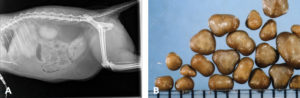

Специалист сможет поставить диагноз после осмотра животного, проведения ультразвукового или рентгенологического исследования. Большой информативностью обладает анализ мочи. Цистит у котов можно определить по уровню рН, количеству белков, при микроскопическом исследовании осадка.

Как ставят диагноз мочекаменная болезнь у котов?

Камни бывают разного происхождения. Все зависит от химического состава. Выделяют:

- Струвиты — растворимые камни. Они состоят из магния, фосфата, аммония;

- Оксалаты кальция — нерастворимые камни. Их удаление требует хирургического вмешательства;

- Цистины;

- Ураты аммония.

В основном встречаются струвиты, но часто бывает, что у одного животного имеются камни разного вида.

- Общий анализ крови;

- Общий анализ мочи;

- Рентген брюшной полости;

- УЗИ.

Непременно нужно выяснить химический состав камней. Это делают в лаборатории ветеринарного центра.